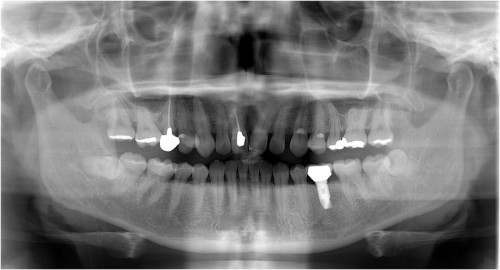

術前

インプラント挿入

土台装着

被せ物装着

同パノラマ写真

被せ物装着後歯肉の盛り上がり